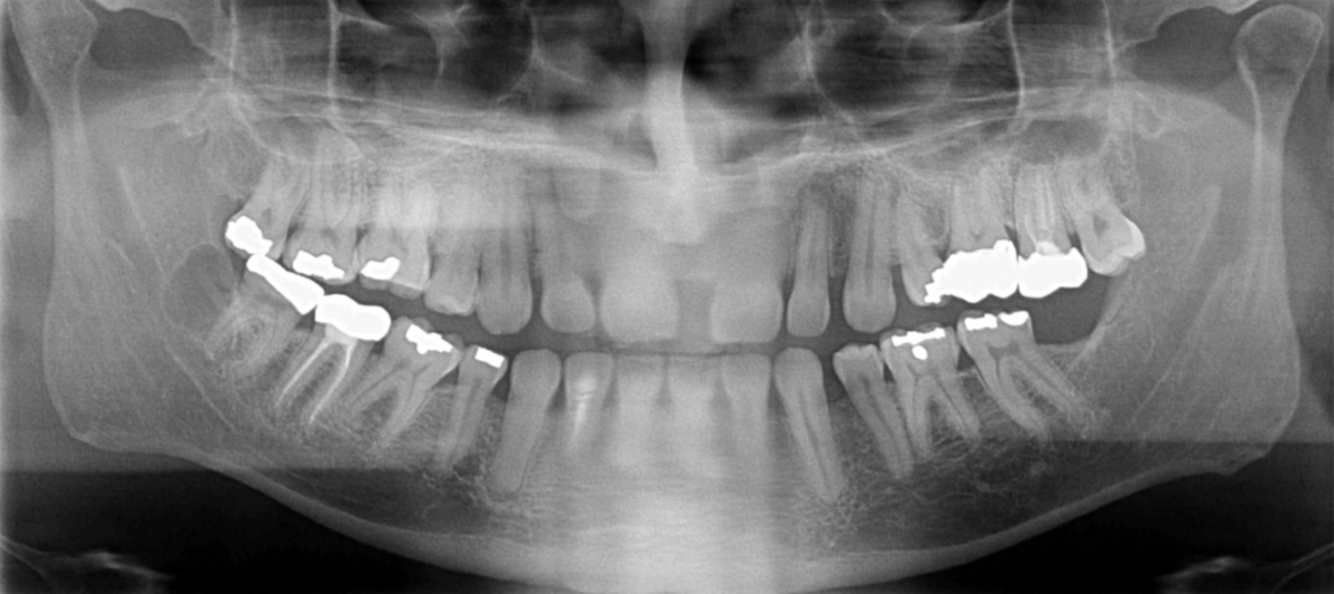

What are the errors in this radiographs? What is the cause of these errors?

A

1. anterior teeth widened & blurred

2. inferior tubercles and meati spread across maxillary sinuses

3. condyles are close to or cut off side image

Cause: Pt too far back